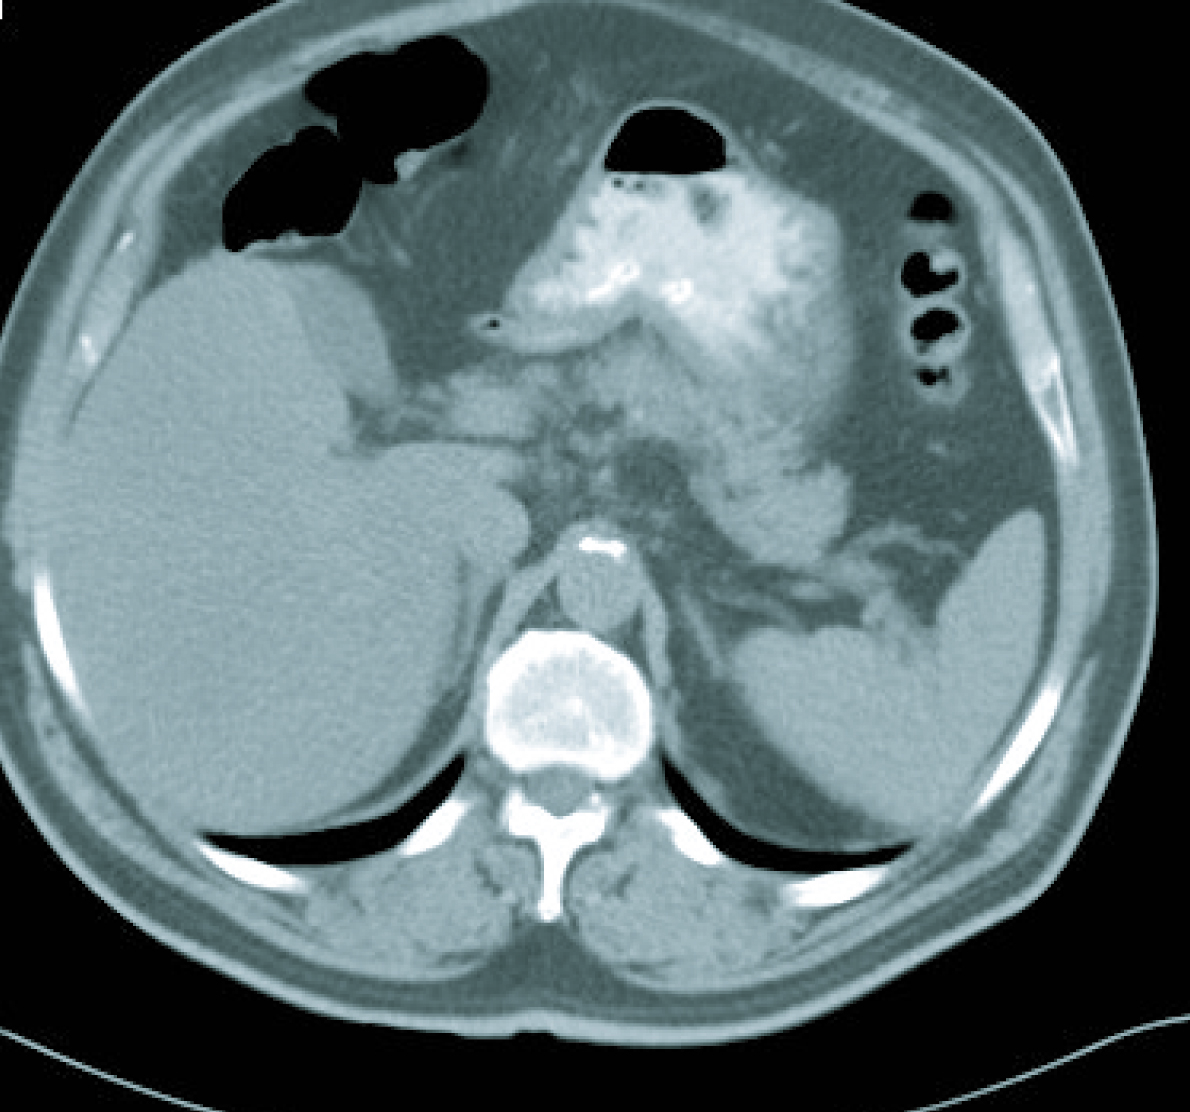

Gastroscopy revealed a 4 cm ulcer in the gastric antrum of uncertain malignancy and a 5 mm ulcer in the body of benign appearance. Anatomical pathology analysis confirmed a diagnosis of intestinal-type gastric adenocarcinoma. It was requested an extended study with CT imaging in order to analyse gastric wall and omental thickening and a number of lymphadenopathies in the gastric, abdominal and retroperitoneal regions (Fig. 1, 2). Analysis showed that tumour markers (CEA and CA 19.9 levels) were not elevated. Given a significant lymphatic component, it was decided to perform an ultrasound-guided fine-needle aspiration (FNA) of the adenopathy, which confirmed a metastatic origin of the adenocarcinoma. Evaluated as an oncology outpatient, the subject presented a maintained general state (with an ECOG 1 performance status), with examination showing a palpable mesogastric mass.

![]() Click for large image | Figure 1. CT imaging at diagnosis. |

![]() Click for large image | Figure 2. CT imaging at diagnosis. |